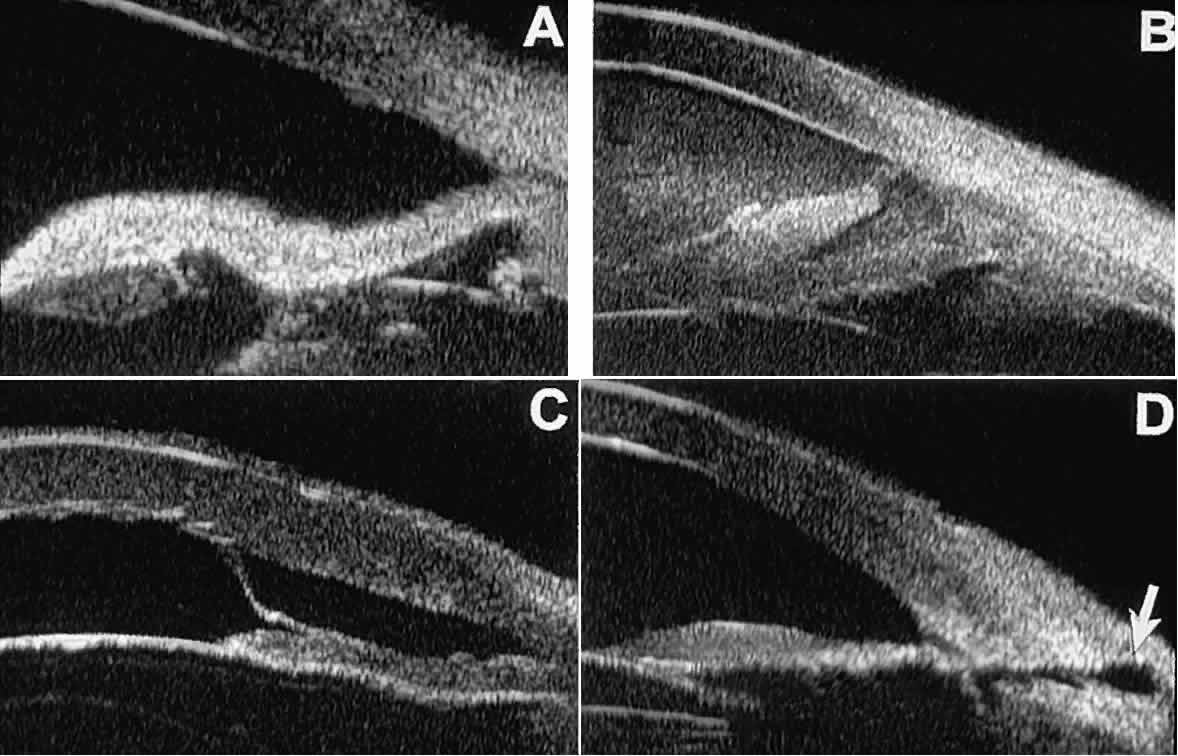

Postoperative UBM imaging of the anatomic changes caused by glaucoma surgery often helps to explain mechanisms of success and failure of the various surgical procedures (Fig. 12).3,4 After laser iridotomy, UBM can show whether the iridotomy is partial thickness (see Fig. 12A) or full thickness (see Fig. 12B) and whether the plane of curvature of the peripheral iris has changed compared with the pretreatment findings. After trabeculectomy (see Fig. 12C), UBM can show whether the scleral aperture is patent or blocked internally, whether the peripheral iridectomy is open or blocked, and whether the filtering bleb is flat, shallow, or deep.9 After tube shunt surgery (see Fig. 12D), UBM can show the position of the tip of the tube and whether its orifice is open or plugged.

Fig. 12. UBM features in glaucomatous eyes after treatment or filtering surgery. A. Incomplete peripheral iridectomy created by laser. B. Full-thickness peripheral iridectomy created by laser. C. Postoperative features of trabeculectomy including peripheral iridectomy, inner scleral defect, thin residual scleral flap, and overlying conjunctival filtering bleb. D. Tube shunt projecting radially into anterior chamber; note that the tube “shadows” deeper structures.

After any type of glaucoma filtering surgery,10 UBM can be used to detect and evaluate the extent of postoperative complications such as ciliochoroidal effusion and cyclodialysis.3,4 In ciliochoroidal effusion (Fig. 13A), UBM shows the ciliary body to be edematous and separated from the sclera by a sonolucent collection of supraciliary fluid. Many ciliochoroidal effusions that are too limited in extent to be detectable by indirect ophthalmoscopy and slit lamp biomicroscopy can be imaged by UBM. In cyclodialysis (see Fig. 13B), UBM shows a well-defined separation between the uveal tissue and the sclera in the region of the scleral spur. The width of the cleft is usually assessed best by means of limbus-concentric images through the region of interest.

Fig. 13. Complications of intraocular surgery. A. Postoperative ciliochoroidal effusion appears as slitlike spaces filled with serous fluid posterior to scleral spur. B. Postoperative cyclodialysis appears as complete separation of iris and ciliary body from sclera in region of scleral spur.